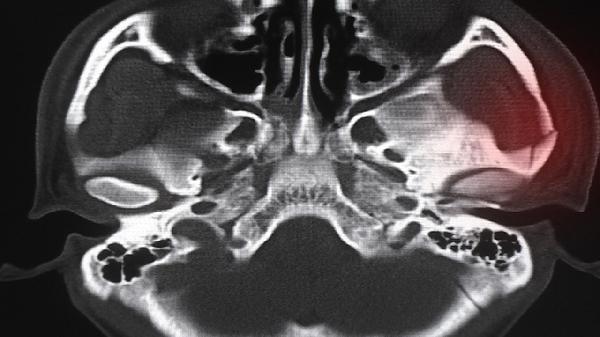

4、肝脏疾病:

肝炎、肝囊肿等肝脏病变会导致肝包膜牵拉痛,表现为持续钝痛伴食欲减退。乙型肝炎需抗病毒治疗如恩替卡韦片,肝囊肿直径超过5厘米需穿刺抽液。患者应严格戒酒,每月复查肝功能指标,蛋白质摄入量每日每公斤体重1.2-1.5克为宜。